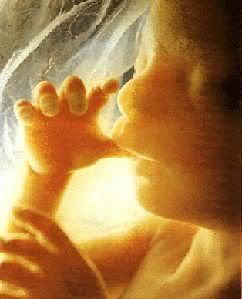

La gravidanza procede bene ed ormai siamo veramente agli sgoccioli. Girovagando per internet guardate cos'ho trovato....incredibile....è veramente il MIRACOLO DELLA VITA

La gravidanza procede bene ed ormai siamo veramente agli sgoccioli. Girovagando per internet guardate cos'ho trovato....incredibile....è veramente il MIRACOLO DELLA VITA

IMMAGINI ECOGRAFIA 3D (cliccate sopra le foto che vedete, ci sono un paio di minifilmati)